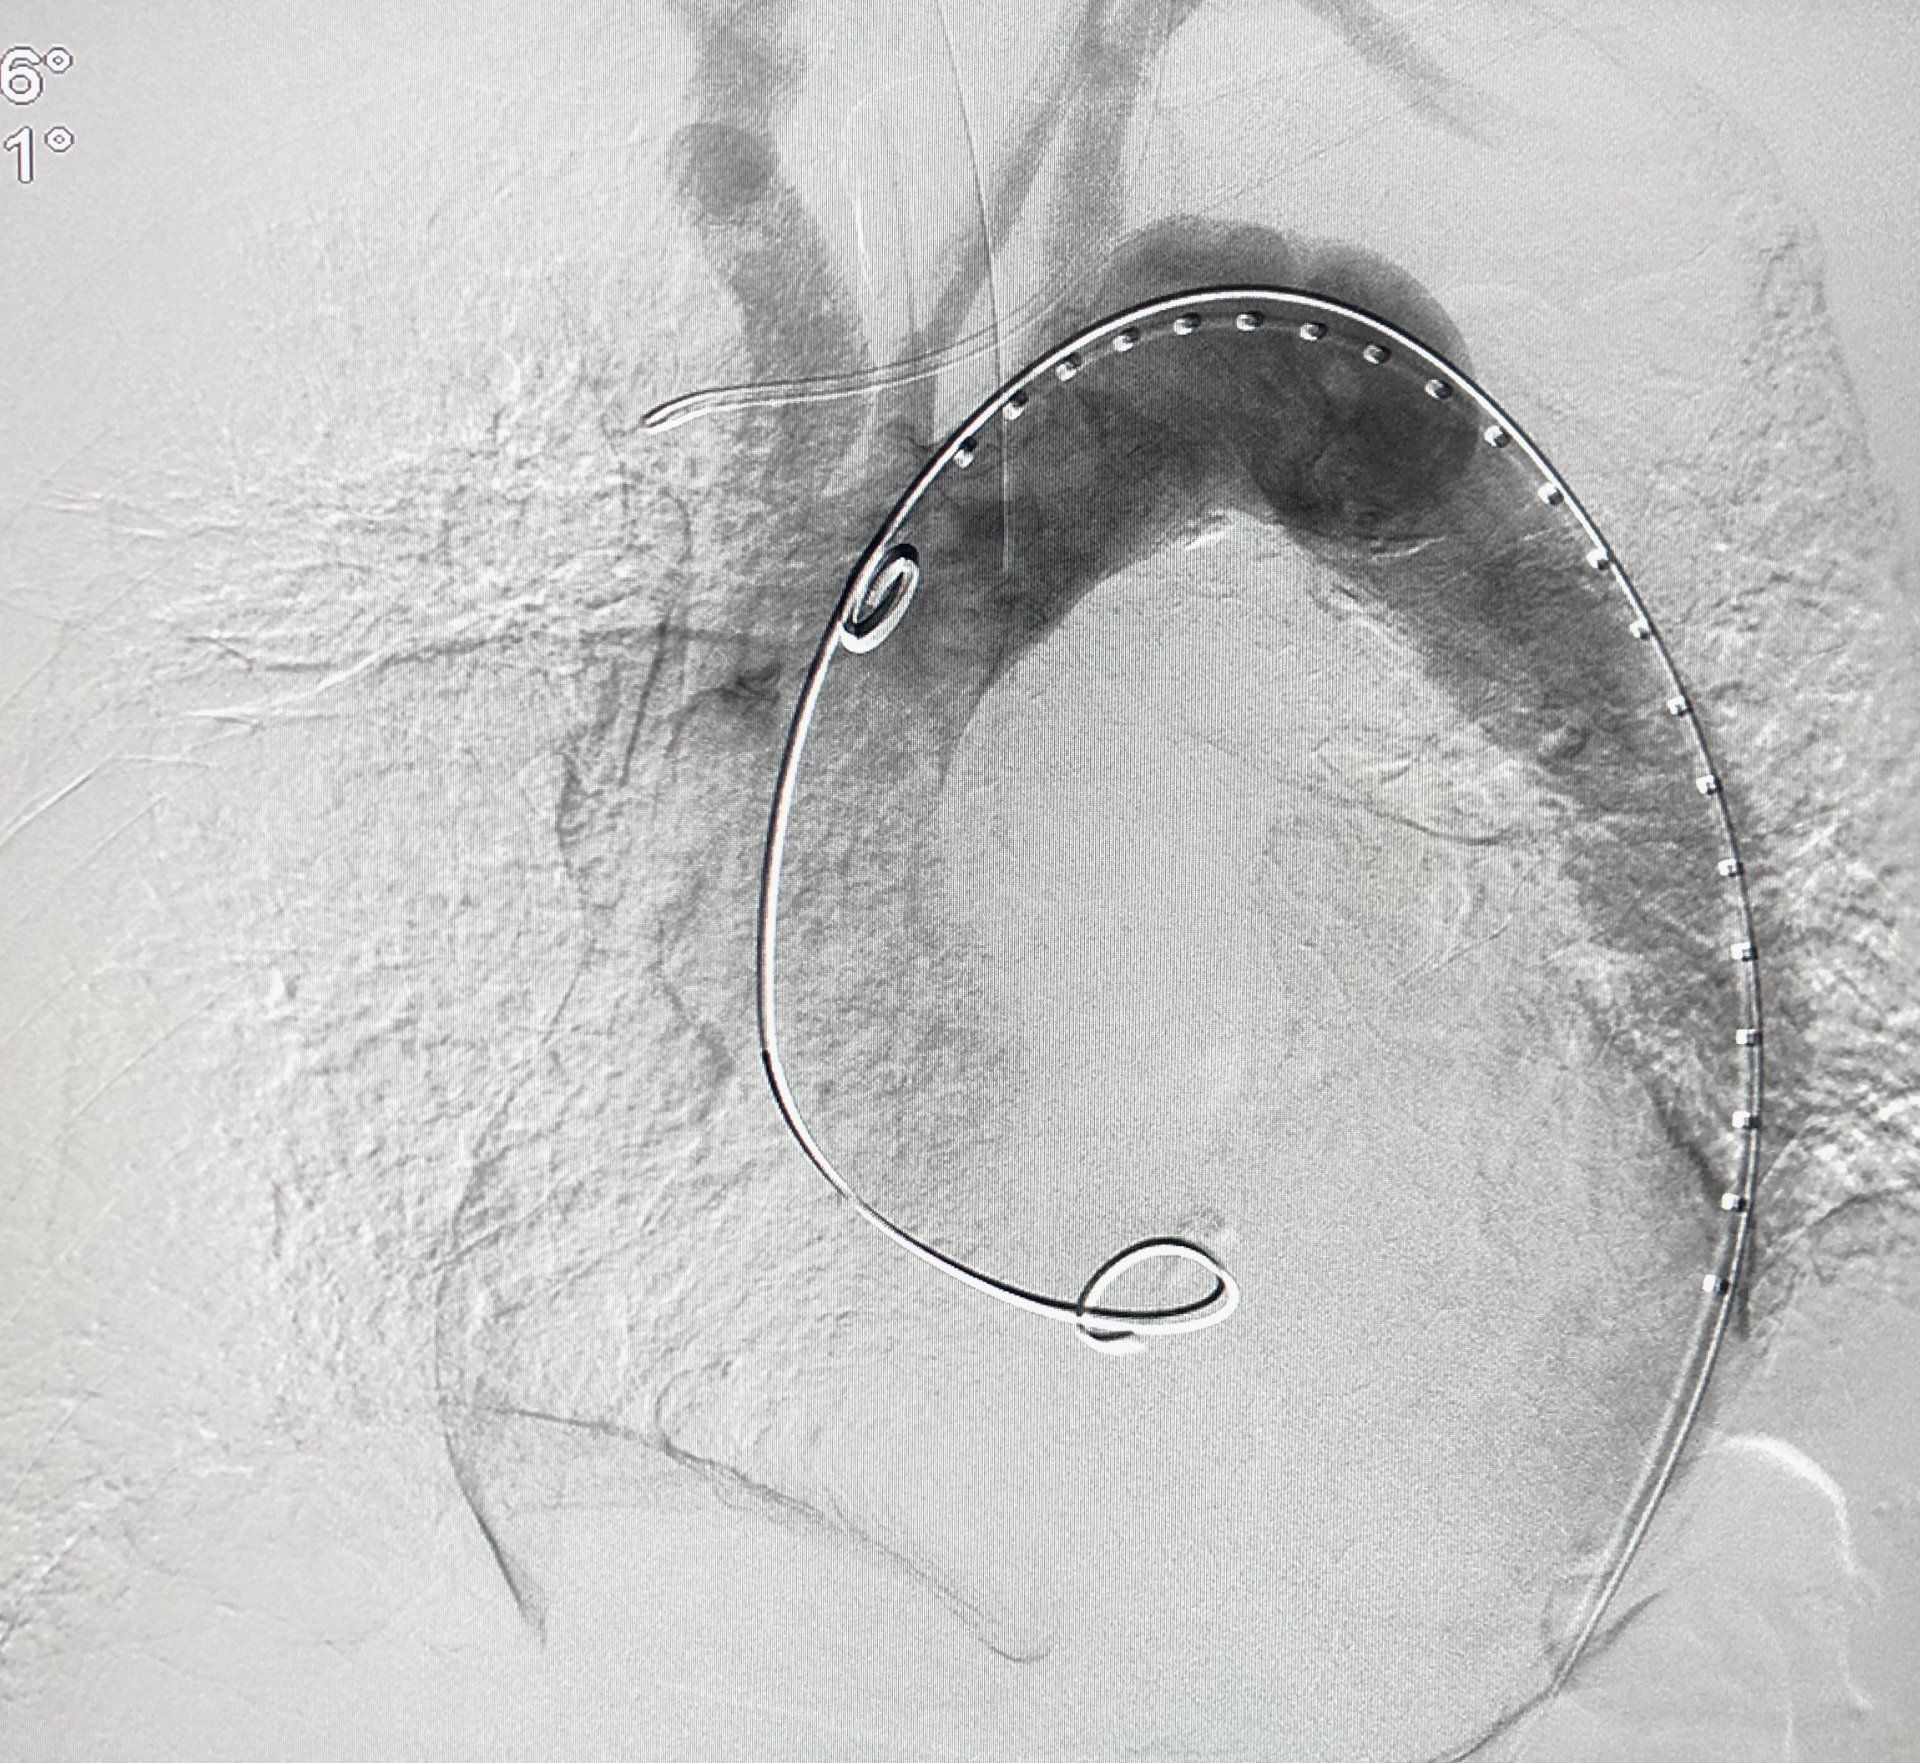

4) Abdominal aortic aneurysm (AAA)